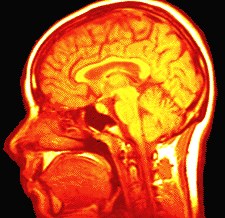

brainB. The Central Nervous System (CNS)

Dr. Joseph P. Hornak (RIT). The Basics of MRI (2003).

[MRI

Image Tumor]

MRI (Magnetic Resonance Imaging): 3-dimensional images created by subjecting body to radio waves under strong magnetic fields. Computers can recreate image of inside of the body.